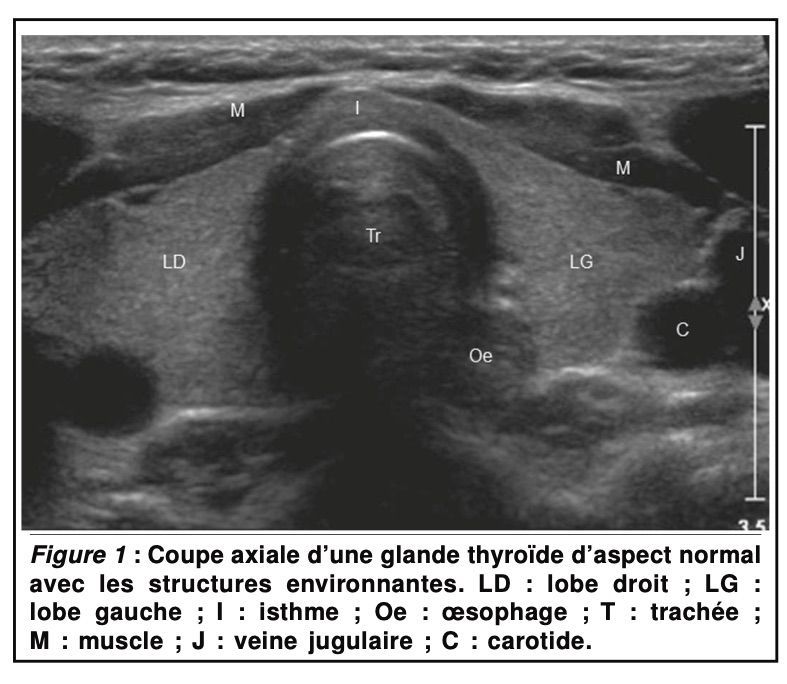

Une échographie de la glande thyroïde qui présente les aspects normale de la thyroïde